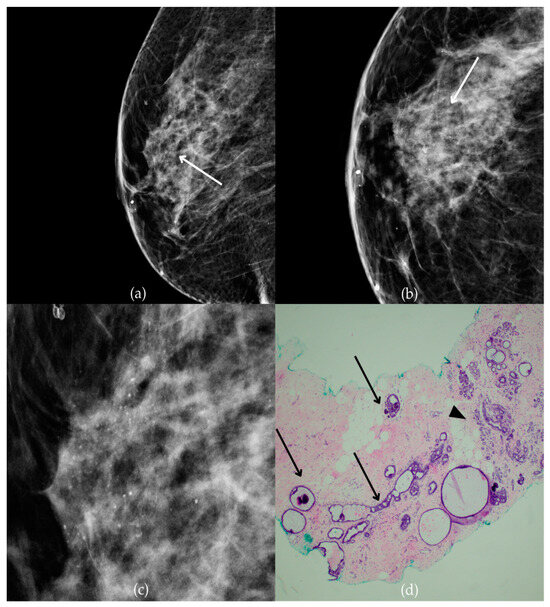

During a screening program, a 64-year-old patient presented with suspicious microcalcifications. The mammogram shown in Figure 3 of the patient’s right breast revealed a segmental distribution of coarse heterogeneous and fine pleomorphic calcifications in the upper outer quadrant, corresponding to a BI-RADS 4 finding. Tissue analysis obtained through VABB confirmed the presence of invasive carcinoma (category B5b). The patient underwent a mastectomy. Postoperative pathology showed only an in situ component, with no evidence of an invasive component, indicating that the invasive component was removed during the biopsy. One year after diagnosis, the follow-up US was reported as BI-RADS 2 classification, indicating benign imaging features.

Figure 3.

Invasive breast cancer. (a) Mediolateral oblique (MLO) mammography view; (b) craniocaudal (CC) mammography view of the right breast showing coarse heterogeneous and fine pleomorphic calcifications (marked with arrows) in the upper outer quadrant, with segmental distribution. (c) Magnified mammographic image of coarse heterogeneous and fine pleomorphic calcifications with segmental distribution. (d) The histopathological image of the biopsy sample shows the characteristic features of invasive cancer (marked with arrow) and ductal carcinoma in situ (DCIS) (marked with arrowhead) (HE staining; 40× magnification).